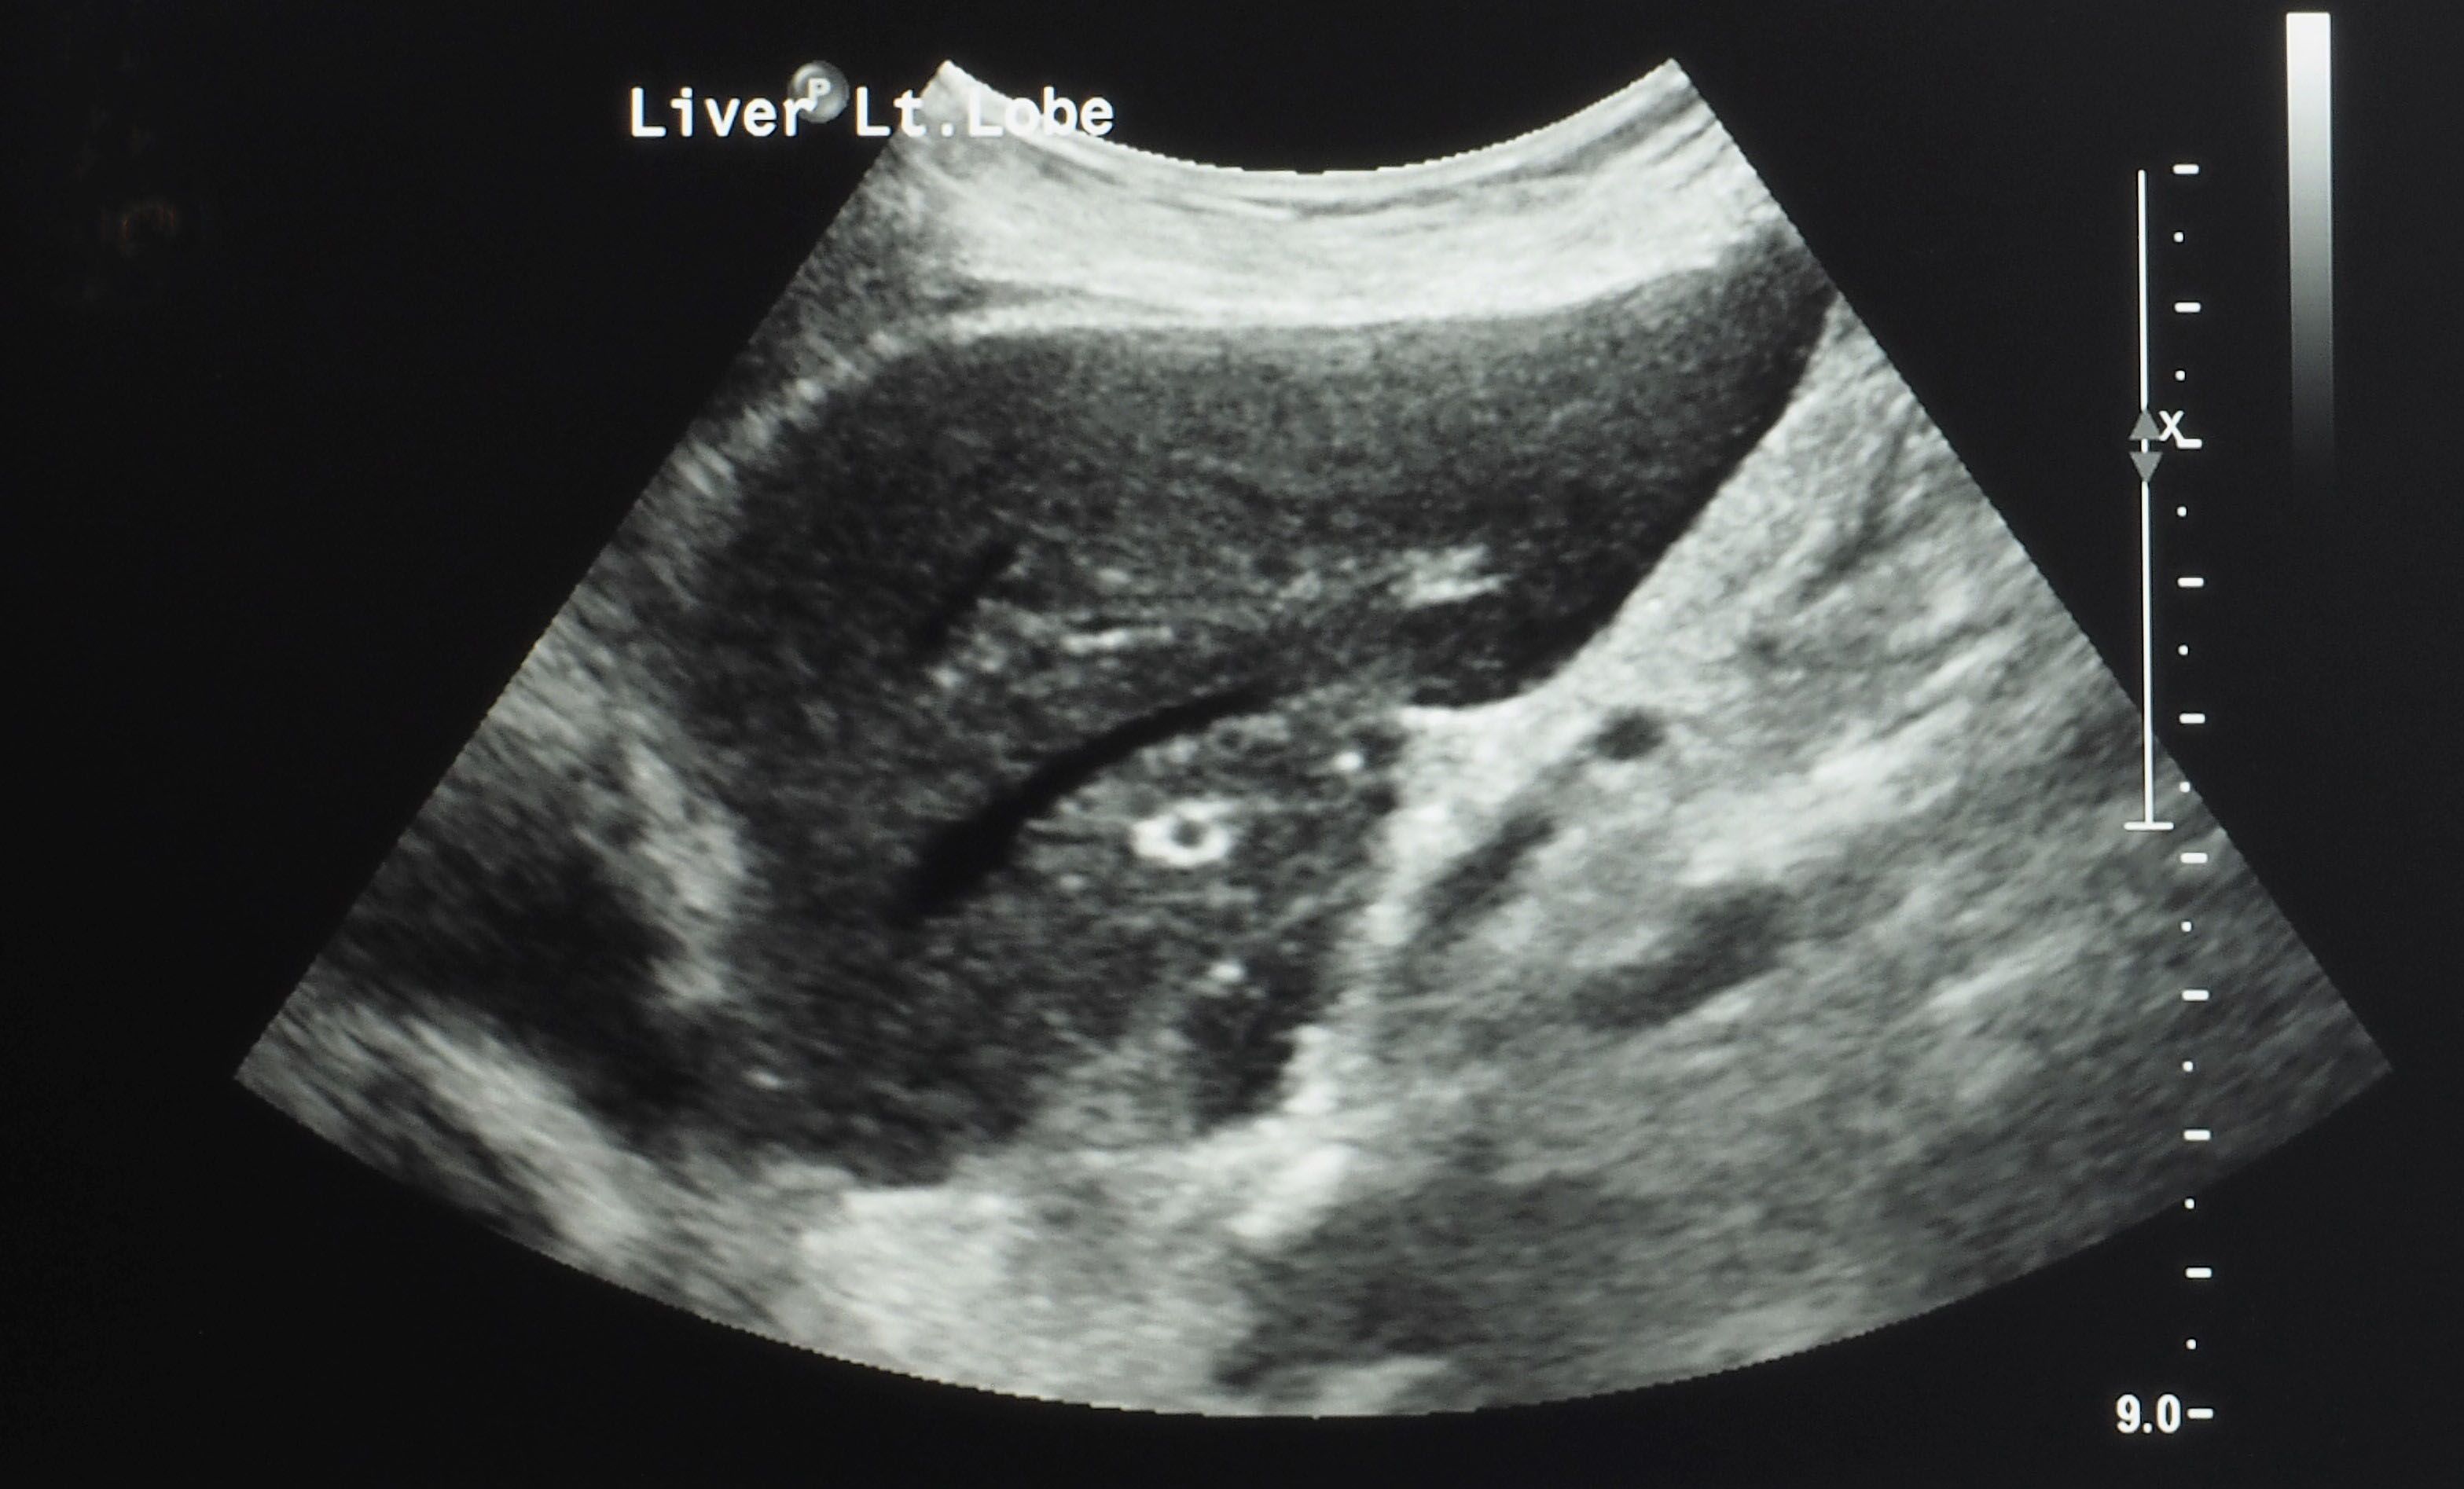

Please be assured that follow-up imaging tests, such as computed tomography (CT) or magnetic resonance imaging (MRI) scans, will be performed to examine your response to these embolization procedures and to monitor the treated tissues over time.